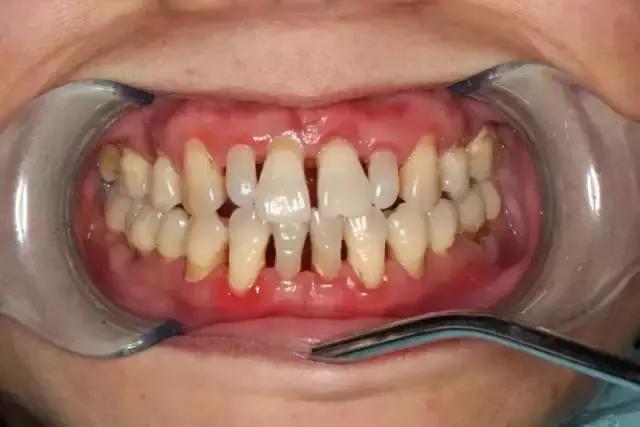

大多数情况都是来自外在的因素(如细菌)导致的出血,比如刷牙不到位导致牙菌斑、牙结石等附着在牙齿表面,长期刺激牙齿周围的牙龈及牙周组织。

虽然起初没有任何的不适症状,但是会使牙龈由健康慢慢变为炎症状态:充血红肿、由坚韧的质地慢慢变得很脆,一旦受到刷牙和咀嚼时的机械摩擦就极易出血。